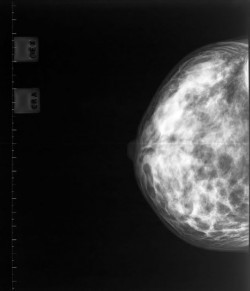

A new study has revealed the benefits of mammograms for women aged 75 years and older.

The research, published in the journal Radiology, shows that mammogram-detected breast cancers are found at an earlier stage; require less treatment; and lead to better survival rates.